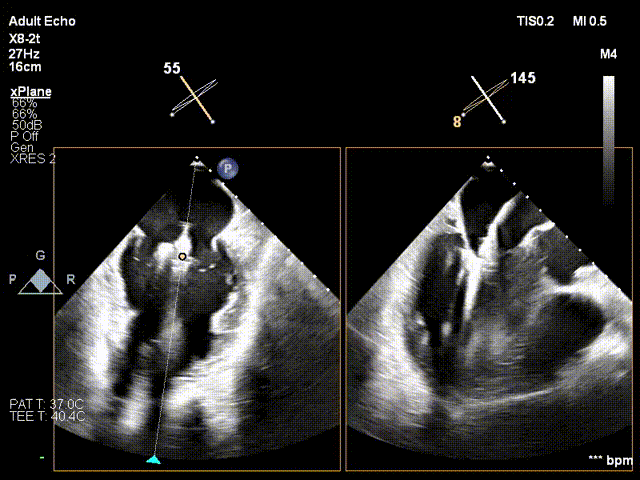

2. 超声引导下,第一套夹子到位,指向后瓣环处

指向后瓣环

3. 3D MPR平面攻入锚定螺丝到三尖瓣环平面

攻螺丝